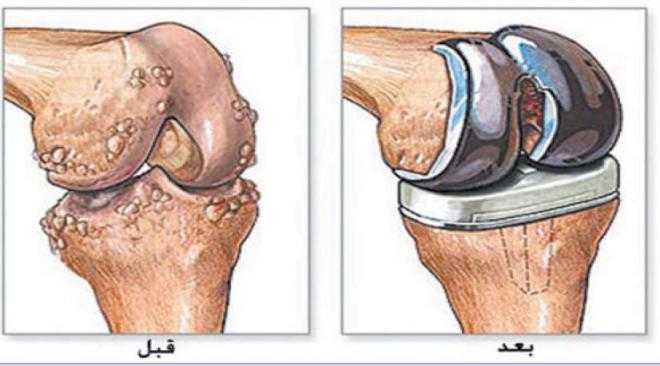

إذا كنت تبحث عن تكلفة عملية الركبة الصناعية ، وتريد التعرف أكثر علي العملية، وجمع مزيد من المعلومات، قبل أن تتخذ الخطوة، فستجد الإجابة على جميع الأسئلة من خلال متابعة المقال التالي حيث تعتبر جراحة تركيب (تبديل) مفصل ركبة صناعي من أنجح جراحات العظام والتى تخلص المريض تماما من آلام خشونة الركبة ولكنها جراحة مكلفة وذات سعر مرتفع.

يخضع المرضى الذين يعانون من تلف شديد في الركبة لاستبدال المفصل الطبيعي باخر صناعي، ويتم هذا الاستبدال من خلال عملية جراحية يتم فيها وصل قطعة من الركبة الصناعية بعظم الفخذ وربط القطعة الأخرى بالجزء العلوي من عظمة الساق، وتوضع قطعة من البولي ايتيلين بين عظم الفخذ والساق لامتصاص الصدمات، وفي 50% من الحالات يتم استبدال الرضفة أيضا.

إن الهدف والوظيفة من استبدال مفصل الركبة هو محاكاة صيغة ومظهر ووظيفة المفصل الطبيعي في أفضل صورة، في هذا السياق يحاول المرء أن يبعد قدر المستطاع القليل من مادة العظم السليم الأمر يقتصر على الأجزاء المهترئة، والتي يتم قصها لاحقاً واستبدالها بسطح معدني وبحسب كمية الضرر في المفصل يتواجد في الوقت الحالي ثلاث أنواع متداولة من استبدال المفصل.

فى هذه الجراحة بعد تخدير المريض, يتم إزالة الأسطح المتهالكة من عظام الفخذ والقصبة (و الصابونه فى بعض الحالات) وإستبدلها بأجزاء صناعية بحيث يختفي الألم الناتج عن إحتكاك العظام ببعضها ويزداد مدى الحركة فى الركبة وتستغرق الجراحة عادة ما بين 60 – 90 دقيقة على حسب صعوبة الحالة والنوع الذي يعتمد علي سعر الركبة الصناعي ومن مزايا هذه الجراحة أن أي أعوجاج (تقوس) بالساق يتم إصلاحه من خلال الجراحة نفسها ويستطيع المريض المشي على رجله فى اليوم التالي للجراحة مباشرة بمساعدة عكازات. ويمكن إجراء هذه الجراحة من خلال جرح صغير كما أن هناك تقنيات حديثة مثل المفصل ثلاثي الأبعاد تستخدم فى بعض الحالات واستخدام الروبوت فى إجراء الجراحة.

ويتكون مفصل الركبة الصناعي من جزء معدني يغطي سطح عظمة الفخذ وآخر يغطي القصبة وبينهما مادة بلاستيكية بيضاء ذات قوة عالية لمنع الأحتكاك بينهم وفى حالات قليلة قد يتم تركيب جزء بلاستيكي يغطي سطح عظمة الصابونة (الردفة) ويتم تثبيت هذه الأجزاء فى العظام عادة بواسطة مادة تسمى الأسمنت العظمي وهناك انواع من مفاصل الركبة الصناعية يتم تركيبها بدون أسمنت طبي ولكن إستخدامها غير شائع نظرا لإرتفاع تكلفنها وعدم ثبوت تميزها عن المفاصل الأسمنتيه.